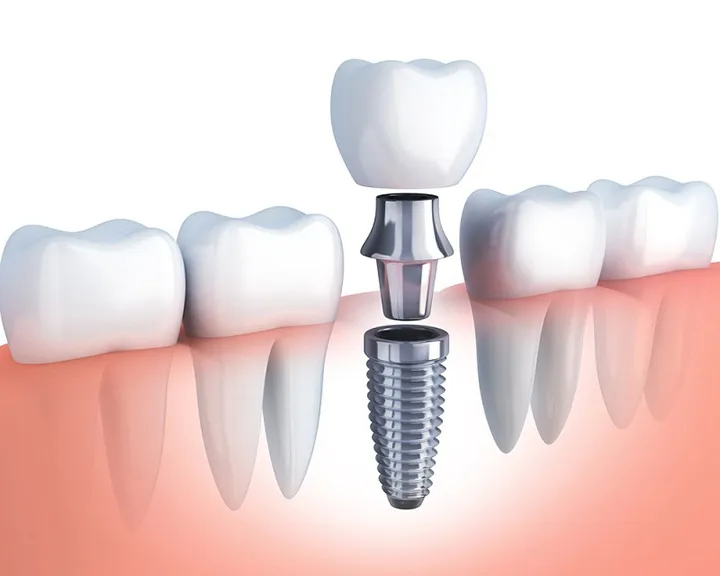

Mất răng là tình trạng phổ biến có thể xảy ra do sâu răng, viêm nha chu, chấn thương hoặc tuổi tác. Không chỉ ảnh hưởng đến